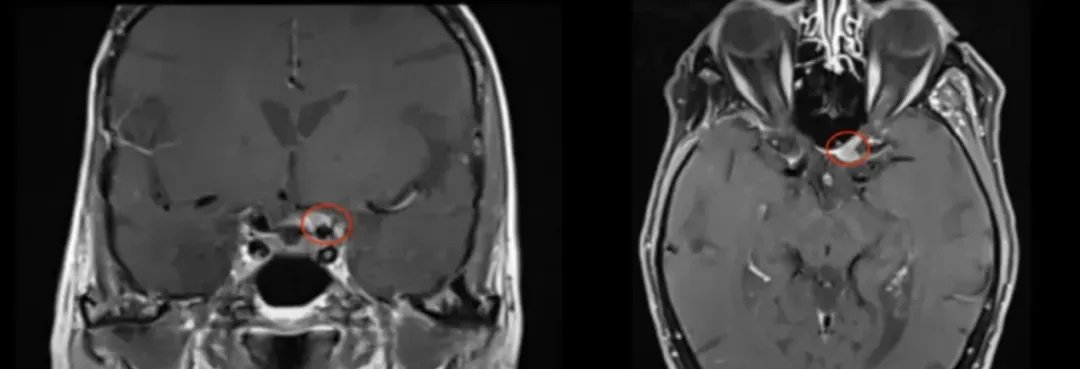

世界神经外科联合会(WFNS)颅底手术委员会前主席Sebastien Froelich教授(塞巴斯蒂安·福洛里希教授,福教授)在手术中采用了内镜辅助下右额下入路肿瘤全切术,为她实施了精准的手术治疗。该手术实现了肿瘤的完全切除,达到了辛普森II级标准。术后,患者的视觉功能得到了显着改善,同时嗅觉功能也保持了完好,没有出现脑嵴液渗漏的情况。

术前及术后磁共振成像。术前preop(A)和术后Postop(C)显示肿瘤完全切除。